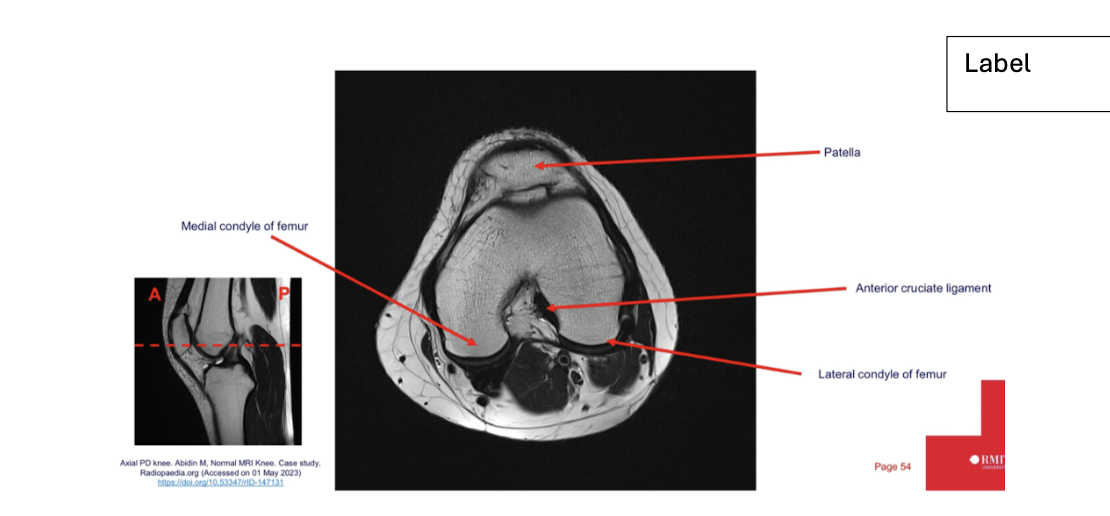

label each

2- lateral and medial condyles of femur

4- vastus lateralis muscle

5-posterior cruciate ligament

6- anterior cruciate ligament

7- medial meniscus of knee

8- lateral meniscus of knee

9-tibia

10-fibula